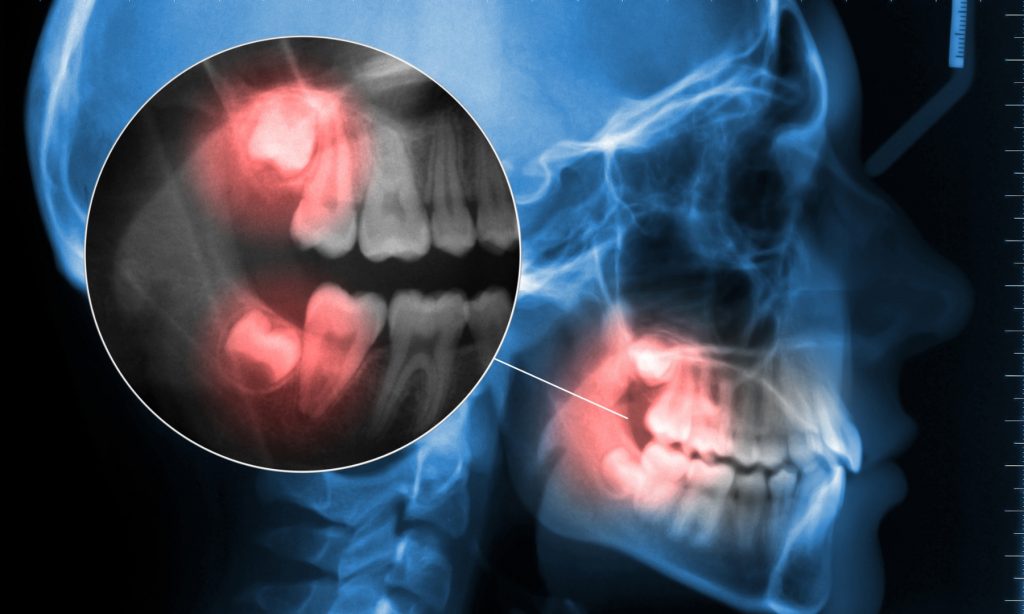

Störfelder sind aber nicht nur in der alternativen Medizin, sondern auch in der Schulmedizin ein Begriff. Denn auch hier heißt es, dass Störfelder lokale Veränderungen sind, die kleine permanente Reize im Körper aussenden und so den Energiefluss sowie die Immunabwehr des Körpers beeinträchtigen. Bekannt sind hier vor allem Störfelder durch Zähne, da diese als Entzündungsherd an vielen Krankheiten beteiligt sein können.

Das Interessante ist aber, dass diese lokalen Störfelder nicht nur punktuelle Ungleichgewichte erzeugen, sondern sich auch auf das gesamte System auswirken. Die berechtigte Frage lautet also: wieso bewirken Zahnentzündungen auch Schmerzen am Fuß?

Wie schon anfänglich erwähnt haben die Zähne eine Sonderstellung im Bereich der Störfelder, auch aus medizinischer Sicht. Einerseits fungieren sie als Entzündungsherd mit allgemeiner Streuwirkung. Andererseits bestehen eben auch besondere Zahnkorrespondenzen zu anderen Organen. Jeder Zahn hat nachweislich eine bestimmte Verbindung zu einem Organ. So können Dickdarm-Beschwerden auch durch einen “faulen” untersten ersten Backenzahn hervorgerufen werden. Diese Verbindungen sind nicht nur Zahnärzten, sondern auch Akupunkteuren bekannt! Untersuchungen zeigen, dass etwa 70% der Störfelder im Kopfbereich bzw. im Zahn-Kiefer-Beriech zu finden sind.